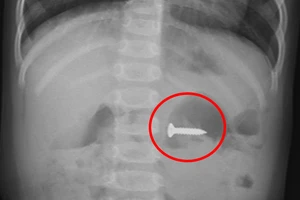

Giật mình khi đang ăn, người đàn ông bị mảnh xương cá diêu hồng cắm vào dây thanh quản 20/04/2022 13:53